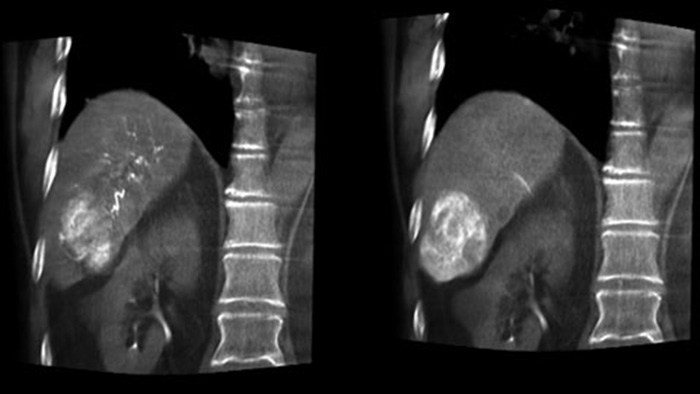

Optimización de la visualización de arterias y tumores con la THC Dual

Visualización óptima de arterias y tumores con la THC Dual

THC Dual permite la adquisición de imágenes en 3D de una fase arterial para visualizar estructuras vasculares y una posarterial (fase retardada) para ver la acumulación del medio de contraste, en un solo paso automático.5